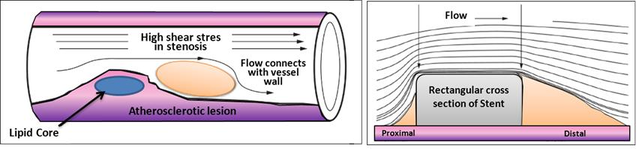

1.2.1.1 Atherosclerosis

Atherosclerosis is a disease in which plaque builds up inside your arteries. Plaque is made up of fat, cholesterol, calcium, and other substances found in the blood. Over time, plaque hardens and narrows your arteries, and in advanced phases of atherosclerosis, plaque becomes vulnerable. This limits the flow of oxygen-rich blood to your organs and other parts of your body and a possible rupture of vulnerable (or unstable) plaque exposes thrombogenic material, such as collagen to the circulation and eventually induces thrombus formation in the lumen. Plaque rupture can occur whenever plaque stress exceeds the plaque strength and thus the prediction of plaque rupture may be augmented by accurate assessment of hemodynamic forces [30]. Atherosclerosis can affect any artery in the body, including arteries in the heart, brain, arms, legs, pelvis, and kidneys, and mainly affects middle and large sized arteries near side branches and at the inner bend of curved segments. At these locations, the average normalized drag force of the flowing blood acting on the vessel wall, the wall shear stress (WSS), is low and/or turbulent leading to endothelial dysfunction and ingress of lipids into the vessel wall, initiating an inflammatory response. Thus in the early phases of the disease WSS can predict locations of plaque initiation and progression[31].

|

| Figure 5: Left, Atherosclerosis lesion. Right, Flow around rectangular section of stent |

In more advanced stages of disease, when plaque growth results in lumen narrowing, the local WSS patterns will change such that certain plaque regions to mainly located upstream- are exposed to elevated WSS[32]. Evidence is accumulating that the elevated WSS influences plaque composition in such a way that it induces local weakening of the plaque, making plaque regions exposed to high WSS prone to rupture[33][34] [35]. Clinical studies confirmed these findings: plaque rupture, both in coronary arteries and carotid arteries are observed more frequently in the upstream of the plaque[36][37][38]. Shear stress with a low mean or maximum value and varying direction (oscillating shear stress) has been associated with development of plaque vulnerability. As a result, different diseases may develop based on which arteries are affected, for example, acute myocardial infarction is mainly triggered by rupture of so-called vulnerable plaques in the coronary arteries linked with the coronary stenosis. In [39] there is a review comparing the localization of atherosclerotic lesions with the distribution of haemodynamic indicators calculated using computational fluid dynamics.

1.2.1.2 Coronary Artery Disease

Coronary artery disease(CAD) is the most common type of heart disease and cause of heart attacks. CAD is caused by abnormal narrowing of the coronary arteries (coronary stenosis) resulting in reduction of blood flow to the heart. The stenosis impedes to deliver oxygen to the heart muscle, which provoking heart attack. This disease is directly related with the atherosclerosis plaque. When stenosis occurs, the common clinical practice for decision taking related to the need (or not) of implanting a stent in a obstructed coronary artery requires the measurement of the Fractional Flow Reserve (FFR). FFR is derived from measuring the ratio of aortic pressure and pressure beyond a stenosis. Stenting is a specialized treatment for coronary arteries that are narrowed or blocked by plaques. It involves placing a balloon into the narrowed portion of the coronary artery with a surrounding wire mesh (stent). When the balloon is expanded, the stent remains in the vessel keeping the plaque pushed outwards, to let blood flow to the heart pass by.

|

| Figure 6: Streamline and wall shear stress in a coronary artery |

In recent years, several alternative methods based on Computational Fluid Dynamics (CFD) have been proposed for non-invasive estimation of coronary blood flow circulation [43]. CFD has been applied to coronary computed tomography angiography for computation of FFR. However, accuracy of method[44][45] and diagnostic accuracy remains suboptimal[46]. The main challenges for such methods are the lack of patient-specific data including anatomy, patient-specific boundary conditions, the condition of the microvasculature of the myocardium, and the large-scale computational resources required for the complex calculations. In [47] pressure gradients are computed using CFD in which the geometry of the aorta is extracted from MRA. Additional MR Phase contrast imaging is performed to measure the velocity which is used as boundary conditions. In [28] lumped parameter models of the heart, systemic circulation and coronary microcirculation are coupled to a patient specific 3D model of the aortic root and epicardial coronary arteries extracted from CTA. Disadvantages of these approaches are that all calculations are performed exclusively in 3D as well as the fact that the calculations cannot be performed during intervention because of the need for CT. Moreover, one vital piece of information is still missing in CFD, namely the condition of the coronary circulatory auto-regulation, also known as the patients cardiac flow reserve. This results in a method that is of high computational complexity. A recent study applied CFD to three dimensional X-ray angiography for the computation of the FFR incorporating the coronary flow reserve[48]. However, this method requires X-ray angiographic imaging during hyperemia which is a burden to the patient. Placing known side effects of adenosine into perspective; reduced blood flow to the heart which might worsen symptoms in patients with coronary heart diseases or even cause a heart attack, this is clearly an undesired situation especially during diagnostic coronary angiography.